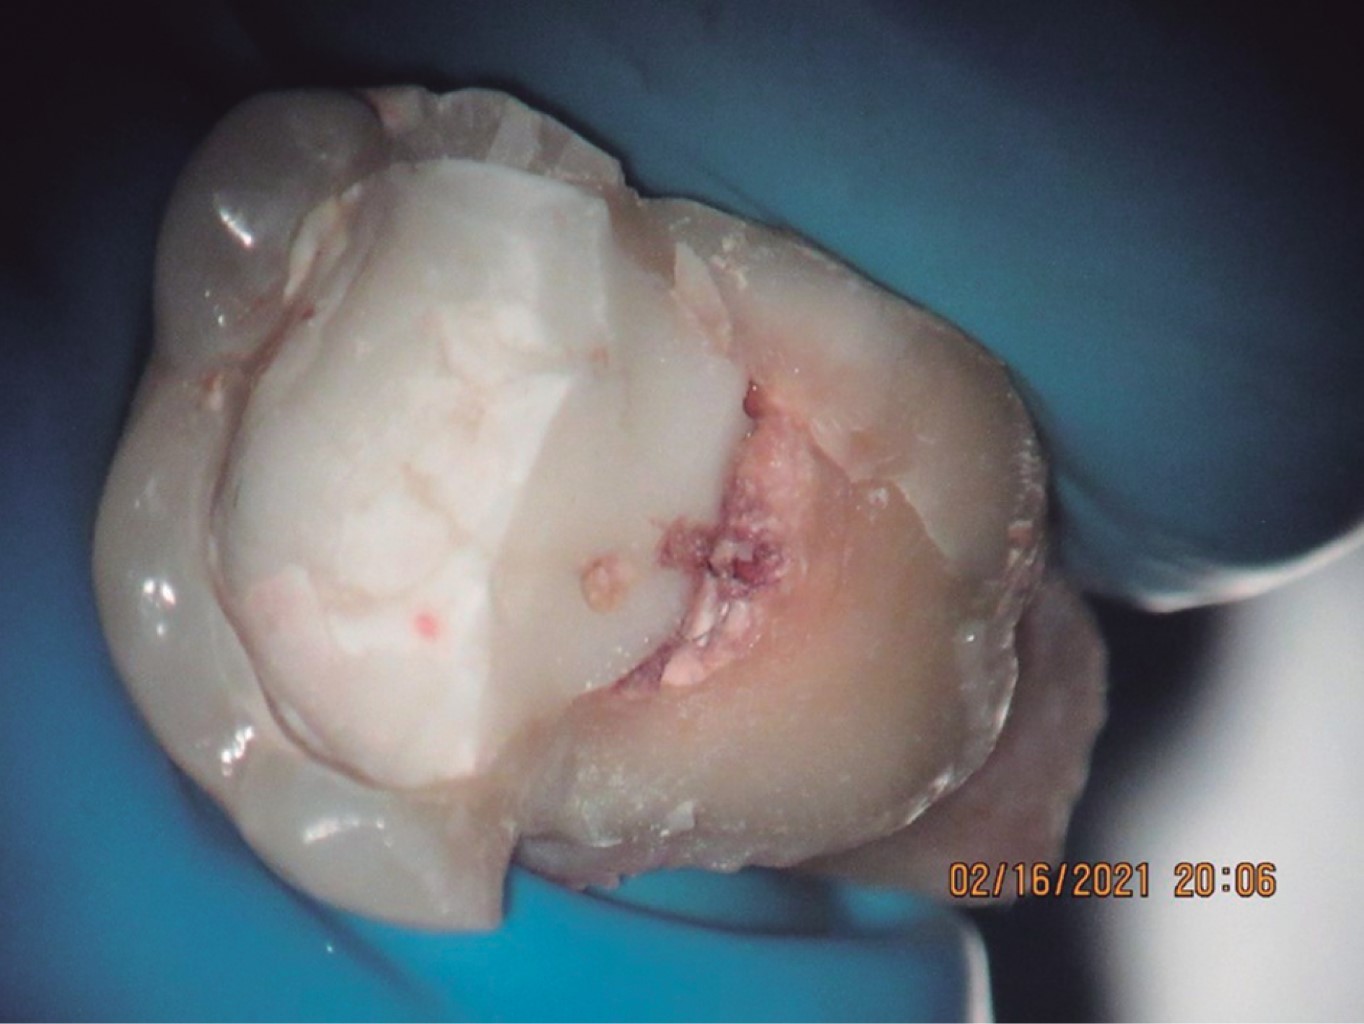

Se seleccionaron únicamente aquellos casos en los que se pudo obtener evidencia clínica, fotográfica y radiográfica de la presencia de por lo menos una fisura vertical o fractura dental que provocara síntomas y que ameritara la extracción del órgano dental por no ser tratable (Figuras 6, 7, 8, 9, 10, 11 y 12).

Se recolectaron en total 26 órganos dentales, los cuales fueron fotografiados con microscopio dental para comprobar la presencia de las fisuras y/o fracturas, en algunos casos se realizó una tinción con azul de metileno para mejorar la visión de las lesiones.

Se agruparon en una tabla por sexo, edad, diente afectado y fecha de presentación, además se estableció si se tenía o no un tratamiento endodóncico en órgano dental afectado y en caso de tener tratamiento endodóncico, se registró si se les había colocado endoposte; también se anotó si el órgano dental estaba restaurado y, de ser así, con qué material; se estableció la dirección de la fisura o fractura en los diferentes planos y, por último, se observó si el diente afectado tenía alguna lesión cariosa (Tabla 1).